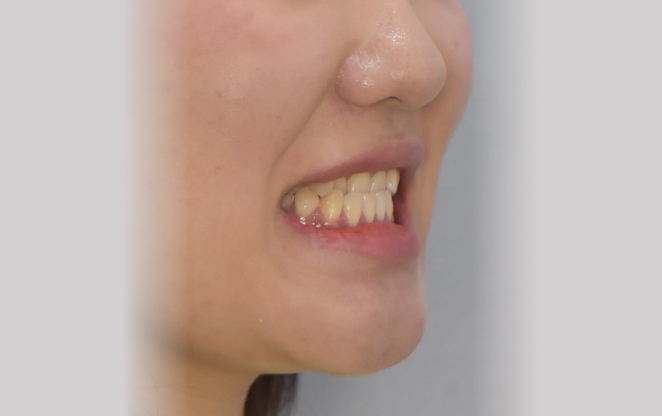

1차 교정

중고생 교정

비발치 교정

비수술 교정

비보철 교정

턱과 얼굴을 빚어나가는

성장교정, 1차교정

아이의 치아는 건강한 미소의 첫걸음이자 자신감의 시작입니다.

초등학생 1차 교정은 영구치가 나오기 전 혼합치열기에 시작하는

교정입니다. 이 중요한 시기에 치아가 제대로 자리 잡을 수 있도록,

아이의 밝은 미래를 위한 준비를 도와드릴게요.

Before

After